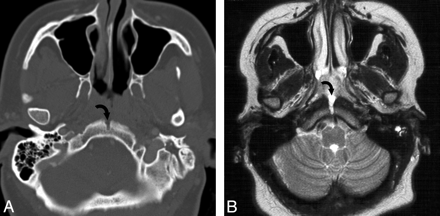

A, A 32-year-old woman presented with a mass in the nasopharynx. MR imaging shows a midline sinus tract extending into the clivus of a pathologically proved extraosseous nasopharyngeal chordoma. Axial bone CT scan shows a midline tract (curved arrow) representing the extension of the extraosseous chordoma into the medial basal canal. B, Axial T2-weighted MR image shows the hyperintense midline sinus tract (curved arrow) extending posteriorly from the nasopharyngeal mass. Note fluid in the left mastoid air cells secondary to obstruction of the eustachian tube due to a nasopharyngeal chordoma.

On T2-weighted sequences, 5 of 5 cases demonstrated heterogeneous hyperintense signal intensity. Scattered areas of very high T2 signal intensity were noted, but all lesions were predominantly mildly hyperintense relative to muscle and less hyperintense compared with CSF. The internal septations on T2-weighted imaging were all uniformly hypointense (Fig 3). Three of the 5 lesions demonstrated a sinus tract extending from the predominant mass lesion posteriorly into the midline clivus (Fig 4). The sinus tract, thought to represent the medial basal canal, was T2 hyperintense in all cases. This sinus tract did not demonstrate enhancement on postcontrast sequences.